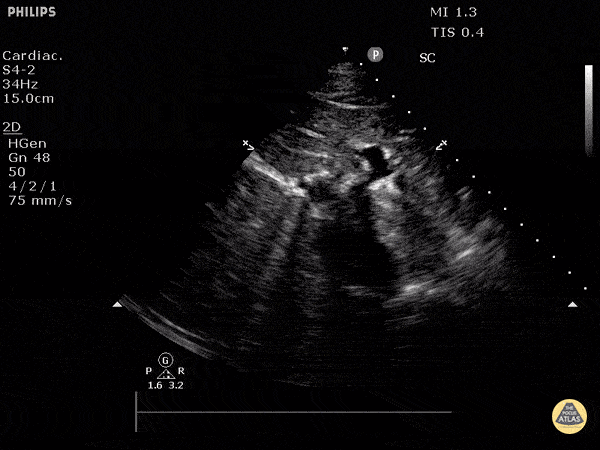

Normal IVC seen in transverse plane using a subxiphoid approach. Justin Bowra MBBS, FACEM, CCPU Emergency Physician, RNSH et al. (Dr. S Fares)